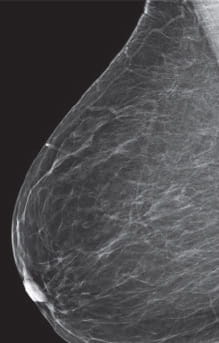

Breast Density Almost Entirely Fatty

Category A: Almost entirely fatty